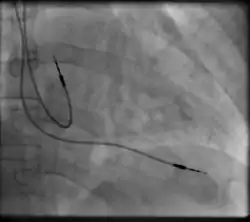

Right atrial and right ventricular leads as visualized under x-ray during a pacemaker implant procedure. The atrial lead is the curved one making a U shape in the upper left part of the figure.